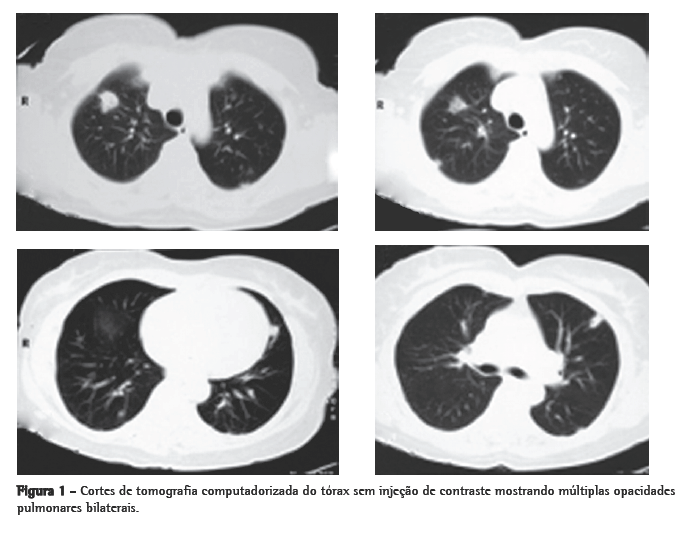

A tomografia computadorizada de tórax de controle após este curso de antibióticos mostrou regressão praticamente total das opacidades (Figura 2). Permaneceu afebril desde o terceiro dia do novo curso de antibióticos. Nenhum microrganismo foi isolado das hemoculturas e culturas do lavado broncoalveolar. A anticoagulação foi suspensa após 20 dias de uso, pela falta de evidência de benefício na síndrome de Lemierre.

Abstract Lemierre's syndrome is characterized by acute oropharyngeal infection, complicated by internal jugular venous thrombosis secondary to septic thrombophlebitis, and by metastatic infections in various distant organs-most commonly in the lungs. We report a case of Lemierre's syndrome in a 56-year-old female who presented with right-sided neck mass and fever. Right internal jugular venous thrombosis was demonstrated on an ultrasound. A computed tomography scan of the chest revealed multiple opacities throughout both lungs. An open surgical biopsy was performed due to suspicion of pulmonary metastases. Anatomopathological examination revealed septic emboli in lung parenchyma. Retrospectively, the patient reported a history of pharyngitis two weeks prior to hospitalization. After the diagnosis had been made, the patient was treated with broad-spectrum antibiotics (cefuroxime for 7 days and azithromycin for 5 days; subsequently, because fever persisted, cefepime for 7 days). One month later, a computed tomography scan of the chest revealed resolution of the opacities.